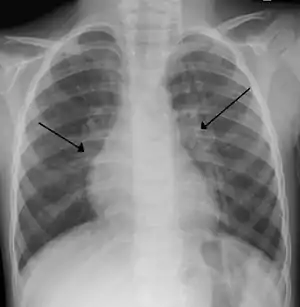

![]() Типові двобічні затемнення на рентгенограмі органів грудної клітки у дитини з тяжким перебігом респіраторно-синцитіальної інфекції Типові двобічні затемнення на рентгенограмі органів грудної клітки у дитини з тяжким перебігом респіраторно-синцитіальної інфекції | |